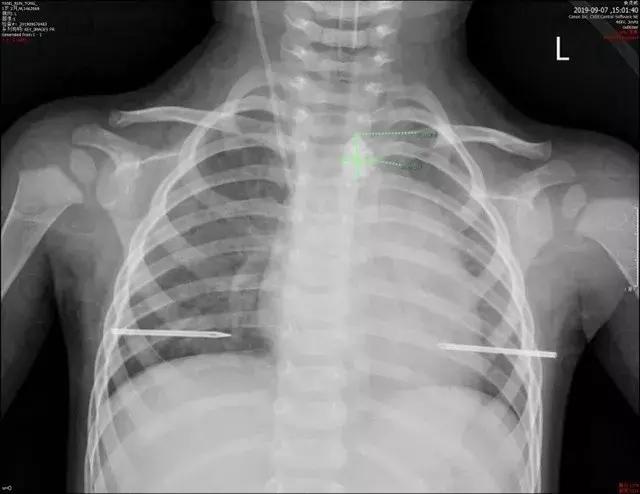

9月7日上午11时,深圳市儿童医院医生收到紧急通知,急诊收入一名1岁2个月的男孩,因“误吞碎玻璃渣3小时”入院,外院胸片检查示“食管上段异物,位于主动脉弓之上约0.7cm,大小约1.2x1.2cm”,入院诊断食管异物。

食管中上段约平第2、3胸椎水平可见一不规则长条状高密度影,大小约13x16mm(左右径x上下径),相应水平食管周围间隙尚清晰。

医生分析后认为,小桐无明显咳嗽、咯血、血压下降等症状,结合CT检查结果,考虑目前食管异物暂未引起主动脉弓损伤,但随着异物存留时间延长,极有可能引起食管穿孔、食管周围间隙感染,最终导致主动脉弓损伤。